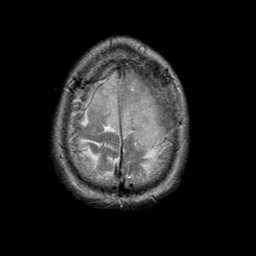

Meningioma, MR Study #1 -- Slice #19

[Home][Help][Clinical] Slice 19